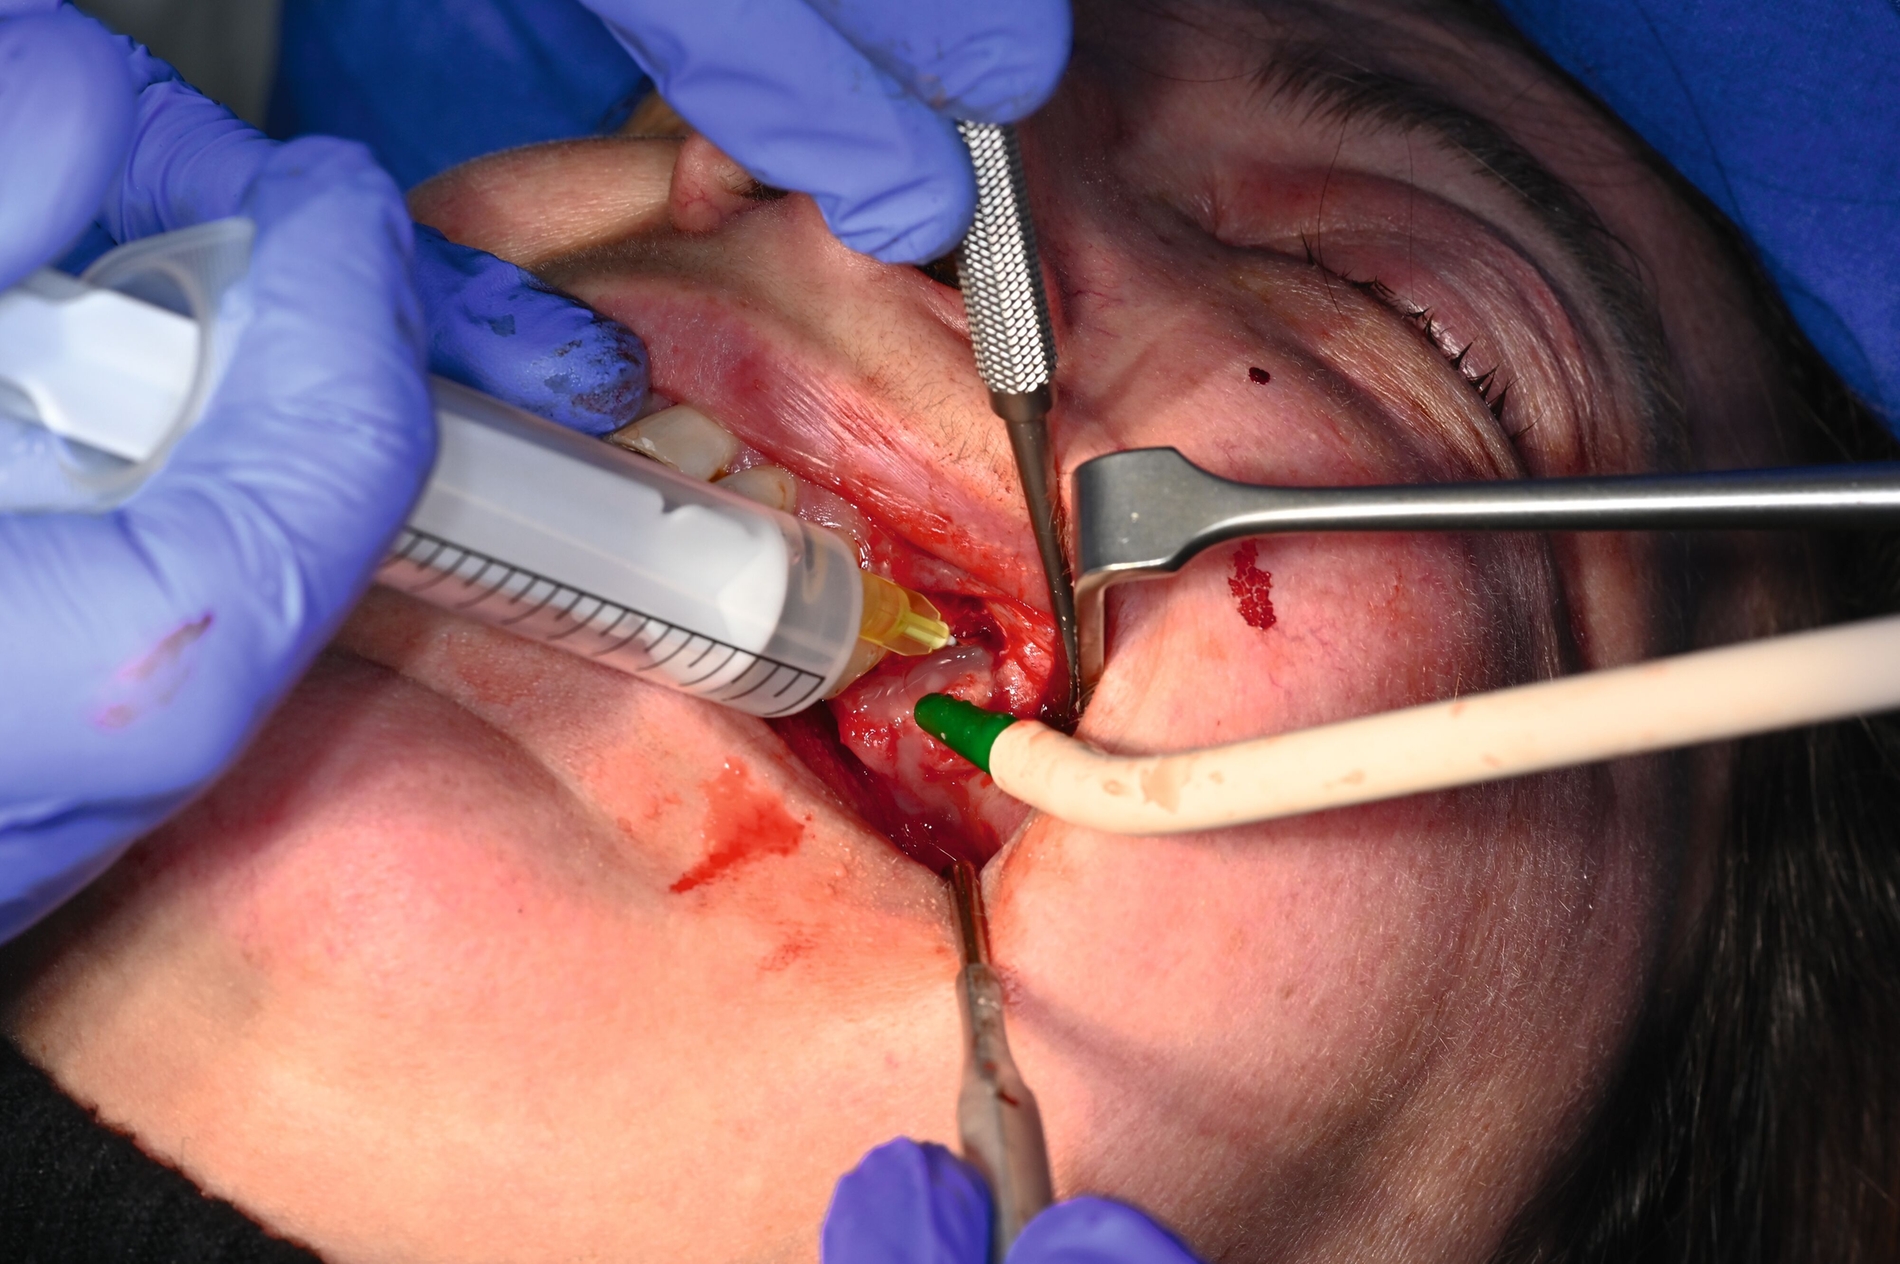

Während der Anmeldungen und Konsilanforderungen wurde notfallmäßig in Lokalanästhesie der in situ verbliebene Wurzelrest 25 mittels Osteotomie entfernt und die Kieferhöhle über die Alveole eröffnet. Das Kieferhöhlenempyem wurde entlastet und ein Drainageröhrchen eingelegt. Es kam zu reichlich Abfluss übelriechenden Eiters (Abbildung 5) und zur merklichen Entlastung für die Patientin. Es wurden Abstriche für die mikrobiologische Untersuchung genommen und die Kieferhöhle wurde wiederholt mit NaCl gespült.